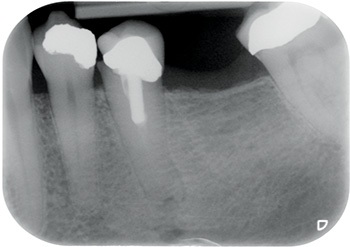

Long Story Short: A Controversial Case?

Figs. 8–10: Fifteen years after restoration.

Well, Frances moved to the other side of the country, but I used to see her initially once a year and then every two years, free of charge, just so I could post updates of the case to Dentaltown. As you can see from the most current X-rays, not only has the implant survived, but the bone around the implant (what many worried would be overloaded and lost) looks even better in 2024 than it did in 2009 when the implant was first restored!

One might expect the loading of the bone around a short implant supporting both a molar and a premolar restoration to be really quite high. Classic teaching suggests bone responds to overload by resorbing. But the bone around this implant looks even better after 15 years of overload than it did when it was first restored.

Perhaps we expect too little of the bone around implants. Perhaps, just like muscle, bone responds to loading by becoming stronger, which explains why Frances’ implant X-ray shows better bone levels after 15 years.